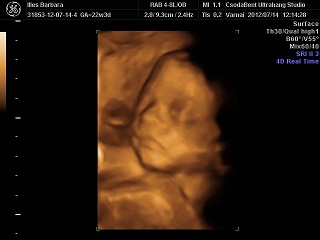

Végre van már 4D-s képünk :)))

szuper, hogy már nincs kánikula, és jó hogy már elviselhető az ínyfájdalmam:))) Kép